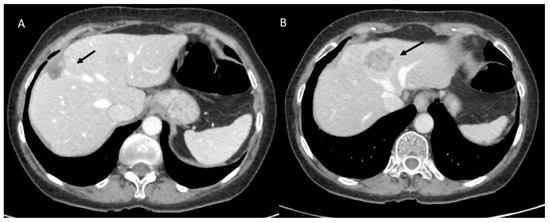

3.2.1. Disease Recurrence

3.2.2. Late Strictures and Ischemic Cholangitis